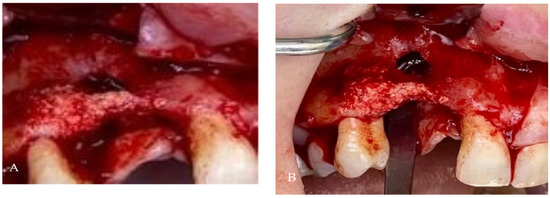

Customized 3D-Printed Titanium Mesh Developed for an Aesthetic Zone to Regenerate a Complex Bone Defect Resulting after a Deficient Odontectomy: A Case Report

Background and Objectives: Alveolar ridge augmentation in the complex bone defect is a popular topic in implantology. Guided bone regeneration (GBR) is one of the most commonly applied methods to reconstruct alveolar bone. The application of a membrane is the fundamental principle of GBR. There are many membrane types used in oral surgery, but the advantage of the titanium mesh is the rigidity which provides space maintenance and prevents contour collapse. The smooth surface also reduces bacterial contamination. Using computer-aided design (CAD) and computer-aided manufacturing (CAM) in dentistry allows us to obtain the perfect architecture form of the mesh, which covers and protects the bone reconstruction. Case presentation: We present a surgical case of a 27-year-old female patient with severe aesthetic bone atrophy after a deficient odontectomy. Based on the GBR clinical applications, the technique consists of bone reconstruction and a customized titanium mesh application. Using mesh titanium in this case presentation was a reliable alternative to perform a lateral alveolar bone augmentation and reconstruct ridge deformities before reaching an ideal implant placement. Conclusions: According to our case report, the customized titanium mesh could be a valuable option for guided bone regeneration in aesthetic maxillary defects. Full article